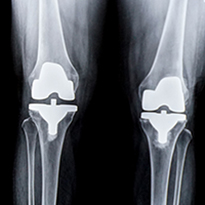

Joint Replacement Surgery